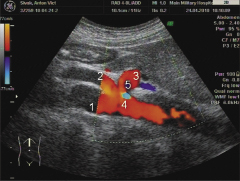

Рис. 2. Эхограмма того же пациента с использованием режима ЦДК: 1 — аорта; 2 — верхняя мезентериальная артерия; 3 — ЧС; 4 — элайзинг-эффект, маркирующий зону стеноза в области сдавления ЧС медиальной дугообразной связкой; 5 — зона турбулентного кровотока за стенозом.

По результатам ультразвукового исследования выявлено изменение формы чревного ствола (ЧС). На рис. 1 видно, что верхняя мезентериальная артерия имеет равномерный просвет, ее диаметр составляет 6 мм. ЧС имеет клиновидную форму с выраженным сужением у основания. Использование режима цветного допплеровского картирования (ЦДК) позволило выявить изменения на картограмме (рис. 2). В области сужения четко визуализировался феномен элайзинга1, соответствующий зоне максимального повышения скорости кровотока внутри стеноза, а дистальнее, в зоне расширения ЧС, выявлена турбулентность кровотока. С помощью импульсной допплерографии обнаружено, что повышение скорости кровотока внутри зоны сужения достигало 255 см/с, что эквивалентно стенозу просвета сосуда 70%. Сужение возникло за счет экстравазального сдавления ЧС расположенной над ним медиальной дугообразной связкой диафрагмы (ее ножки охватывают аорту на входе в брюшную полость двумя ветвями, расходящимися под острым углом) вследствие врожденной анатомической особенности строения этой зоны. Пациенту рекомендовано наблюдение и при необходимости — оперативное устранение стеноза2.